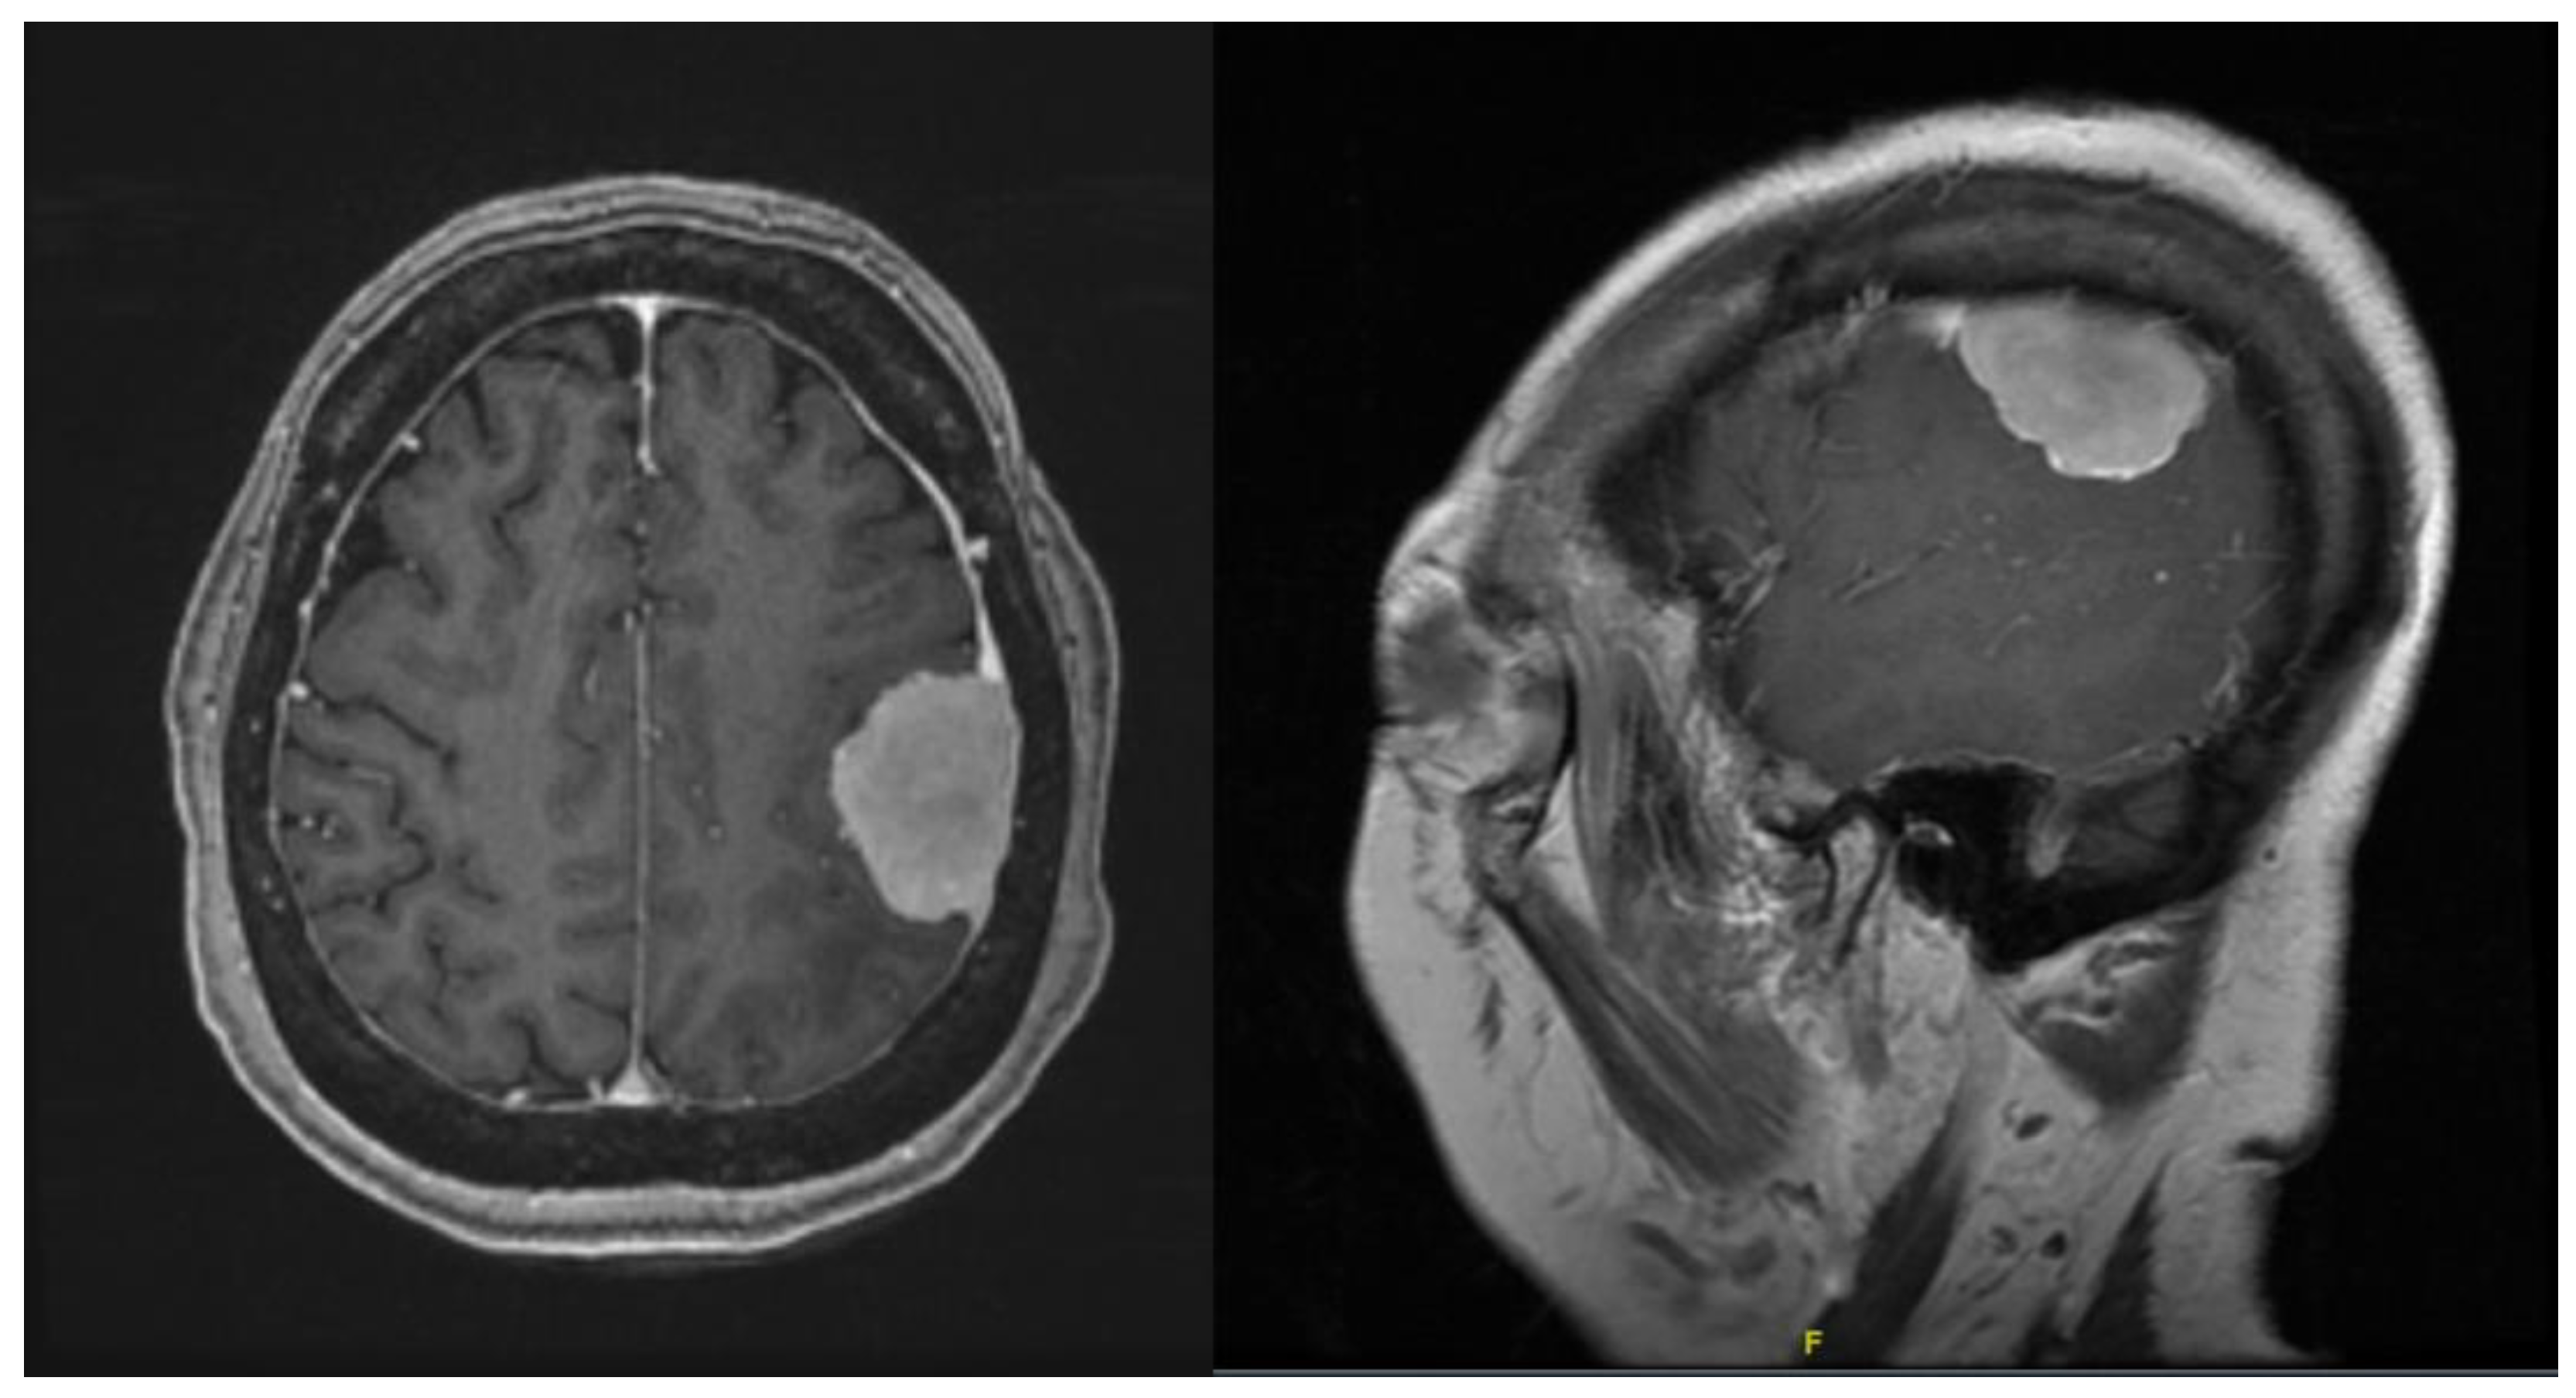

The next patient was a 67-year-old female presenting with right-sided weakness. On examination, she was noted to have grade 3/5 on the right upper and lower limb. MRI brain with contrast showed a 3.6 × 2.7 × 1.4 cm left frontal convexity tumour with features consistent of that being a meningioma (Figure 4). Patient was counselled for craniotomy and resection of tumour under general anaesthesia.

The next patient was a 57-year-old male presenting with right-sided weakness and short-term memory loss. On examination, he was noted to have grade 4/5 on the right upper and lower right limb. MRI brain with contrast showed a 6.6 × 5.2 × 5.1 cm intra-axial tumour in the left fronto-parietal region (Figure 7). Diffusion imaging tractography (DTI) was also performed on this patient.

Figure 4. Contrasted T1 MRI showing homogenously enhancing frontal convexity meningioma.

Figure 7. Contrasted T1 MRI showing the intra-axial cystic tumour.